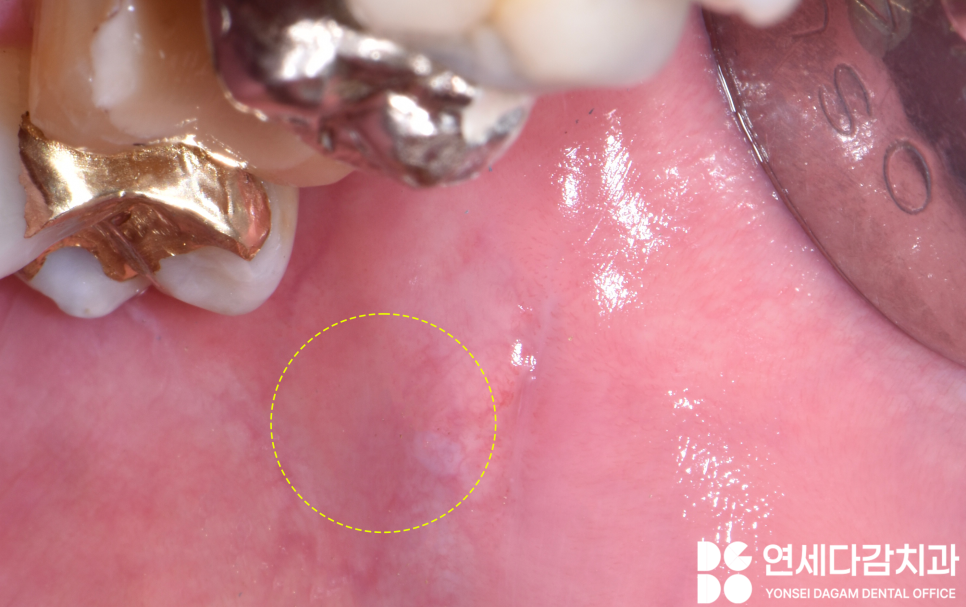

입술에 몽우리 같은 것이

보이는데요.

이것은 외상성 섬유종으로

확인되었는데요.

이름에서 알 수 있듯이

외상에 의해 생기는 경우가

많습니다.